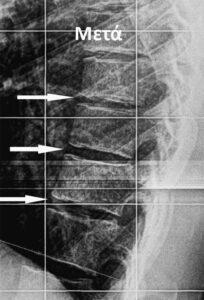

Μια άλλη χρήση του είναι σε περιπτώσεις σταθερών συμπιεστικών καταγμάτων σπονδυλικής στήλης. Εξαιτίας του κατάγματος δημιουργείται μια πρόσθια παραμόρφωση του σπονδυλικού σώματος.

Όταν το κάταγμα είναι φρέσκο δηλαδή τις πρώτες 3 εβδομάδες και πριν αρχίσει να πωρώνεται, η χρήση του κηδεμόνα βοηθάει στην σωστότερη ανάπλαση του σώματος του σπονδύλου.

Επίσης αποφεύγεται η περαιτέρω μείωση του ύψους του από την απορρόφηση του αιματώματος και την περαιτέρω συμπίεση του.

Η χρήση του είναι απόλυτα ενδεδειγμένη στα Οστεοπορωτικά κατάγματα